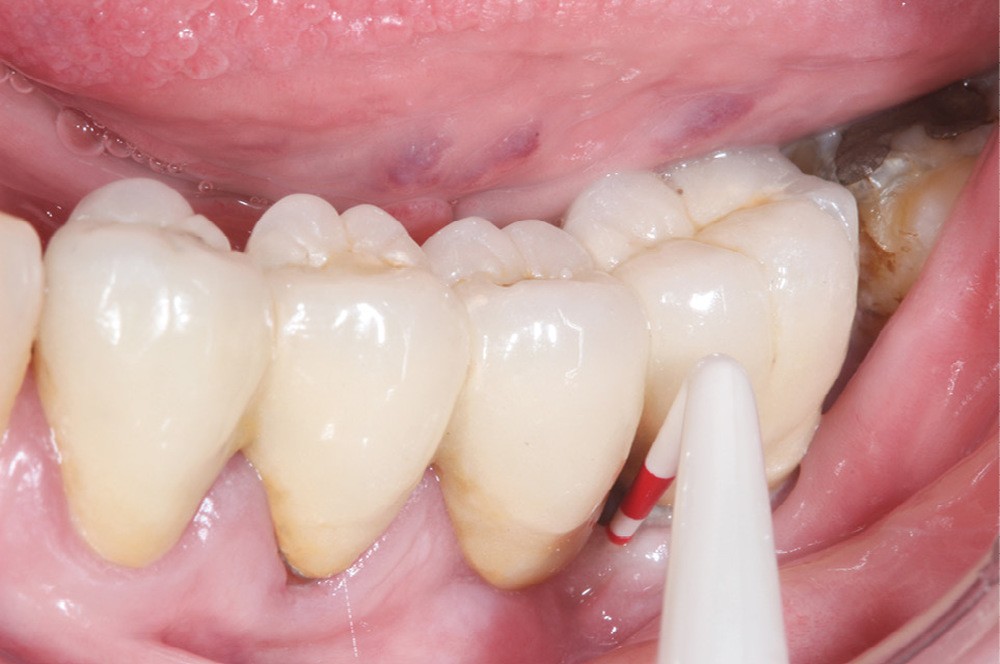

Le mode d’assemblage (prothèse vissée ou scellée) retenu peut aussi influencer la survenue d’une péri-implantite, avec une corrélation importante entre survenue de péri-implantite et présence d’excès de ciment de scellement [13, 14]. Une connexion dent-implant (prothèse dento-implanto-portée) est à proscrire, car plus propice aux péri-implantites et échecs mécaniques (fig. 4 et 5) [15, 16].